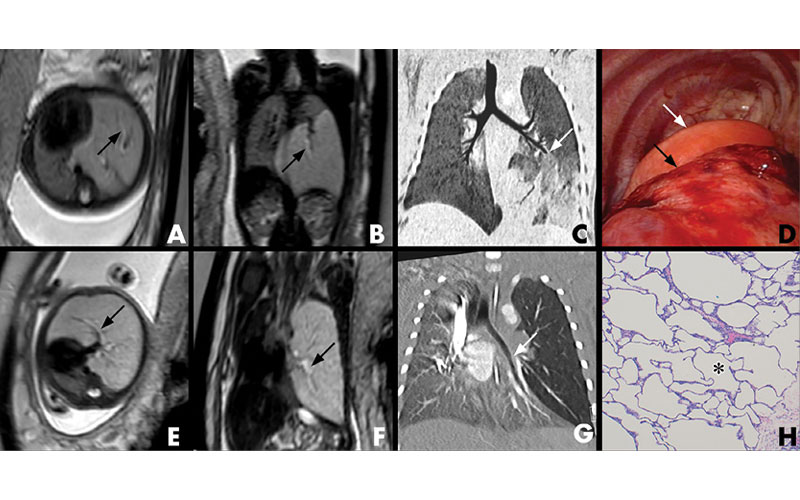

In a Radiology study published in May, researchers found that an MR imaging characteristic called the hyperintense bronchus sign (HBS) is a marker of a blocked airway and is observed with more prevalence in certain congenital lung malformations.

“In our analysis of lung lesions in prenatal MRI scans, we identified a linear T2 hyperintensity within the lungs,” said co-author Gregor Kasprian, MD, associate professor of radiology in the Department of Biomedical Imaging and Image-Guided Therapy at the Medical University of Vienna. “We call this the hyperintense bronchus sign.”

“Our findings indicate that the HBS is caused by airway obstruction, and we can use it to distinguish, with a high sensitivity, among lesions such as bronchial atresia and sequestration, and CCAM,” said lead author Florian Prayer, MD, who is also a PhD student at the Medical University of Vienna.

The HBS was most prevalent in cases of bronchial atresia (BA), followed by bronchopulmonary sequestration (BPS), and was most visible up to 26 gestational weeks.

“We found the HBS in almost 80% of BA cases and in 70% of BPS cases,” Dr. Prayer said. “This can help to distinguish BA and BPS from other lung lesions, not only early in pregnancies but also non-invasively.”